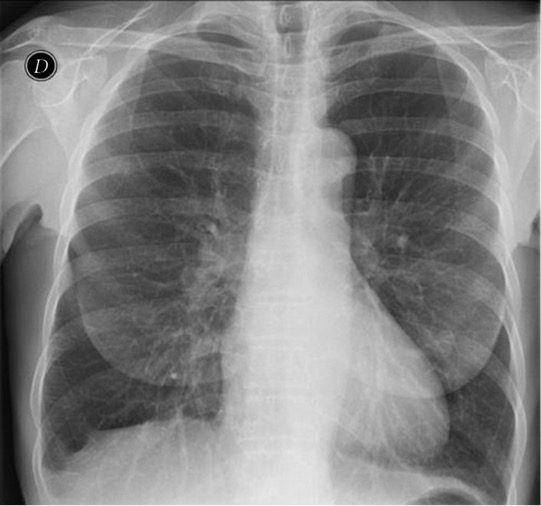

Solución: Es un estudio Normal. Silueta cardiomediastínica y parénquimas pulmonares sin alteraciones significativas.